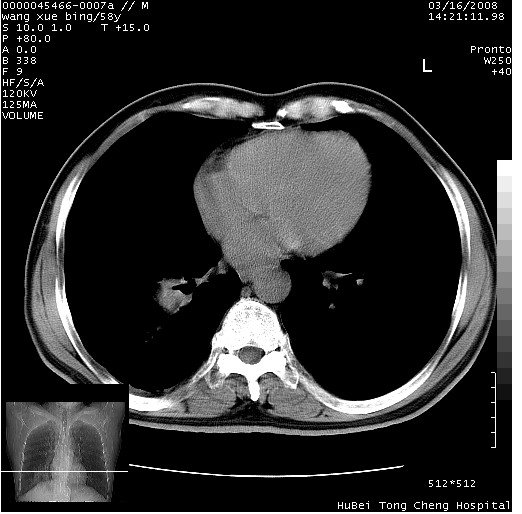

胸部ct轴位平扫(层厚10mm,螺距1.5,重建间隔10mm),图像如下:

右肺下叶团块及不规则空洞,内壁不规则,外缘见粗长毛刺,临近胸膜明显增厚并与病灶关系密切。支持考虑:右肺肺脓肿!建议穿刺病理检查待除外周围型肺癌!

右肺下叶见不规则厚壁空洞,内壁不规则,外缘见粗长毛刺,临近胸膜明显增厚并与病灶关系密切。支持考虑:周围型肺癌!

右肺下叶周围型肺癌伴空洞形成!征象比较明显!分叶、毛刺、胸膜凹陷征、厚壁空洞,壁结节!

空洞壁厚,不规则,其内可见壁结节,周围可见毛刺及阻塞性炎变,多考虑癌性病变.